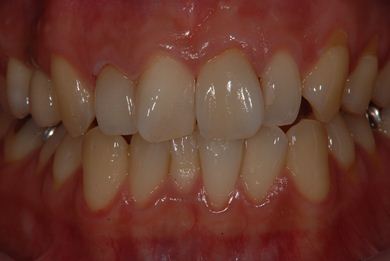

インプラントの症例写真 IMPLANT

インプラント治療+セラミック治療

| 治療内容 | インプラント1本、メタルボンドセラミッククラウン1本、オールセラミッククラウン2本(オールセラミック用土台2本) | ||||||||||||||||||||||||||||||||

| 治療期間 | 1年6ヶ月 |